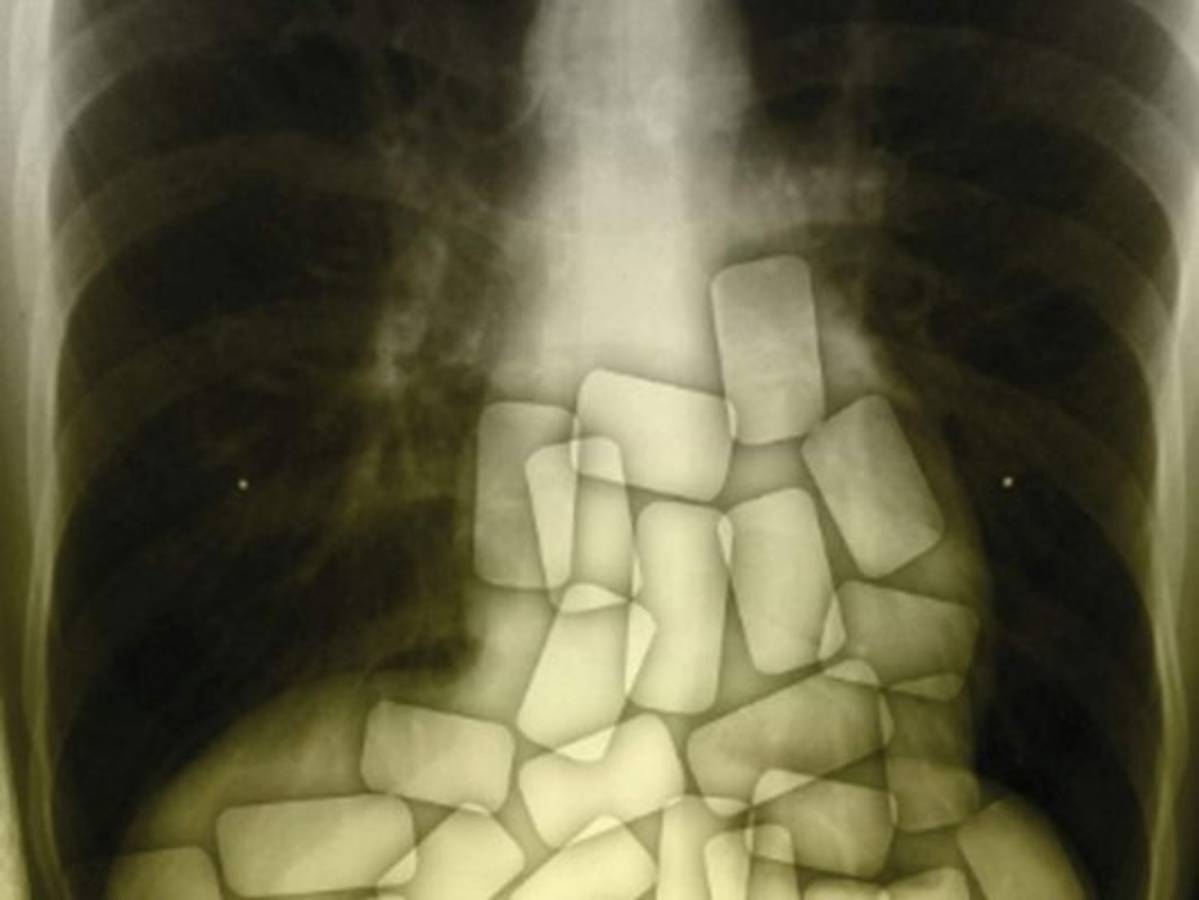

Bajo la supervisión de los traficantes, Bernardo ingería las cápsulas de cocaína en un apartamento en Burgos (norte de España), para ser transportado en un vehículo hasta Suiza, donde expulsaba la droga.

Pero en julio de 2014, 'cuando ya llevaba 67 cápsulas ingeridas, Fernando comenzó a sentirse mal' y 'comenzó a vomitar y tener convulsiones', pero la pareja que lo vigilaba no pidió asistencia médica, sino que se limitó a notificar al jefe, según el auto.